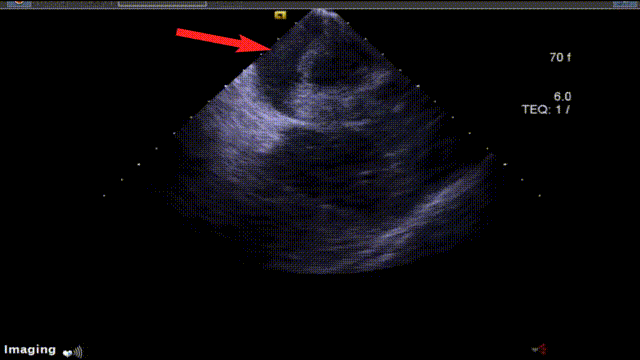

2025-04-22 超声心动图:LA 45mm;IVS 6mm;LVEF 59。65%。

食道超声诊断:1、左房、右房及左心耳未见附壁血栓;2、二尖瓣、三尖瓣返流。

术前经食道超声心动图检查:双房及双心耳内未见血栓,评估左心耳形态及大小

ICE引导房间隔穿刺

ICE下穿房间隔